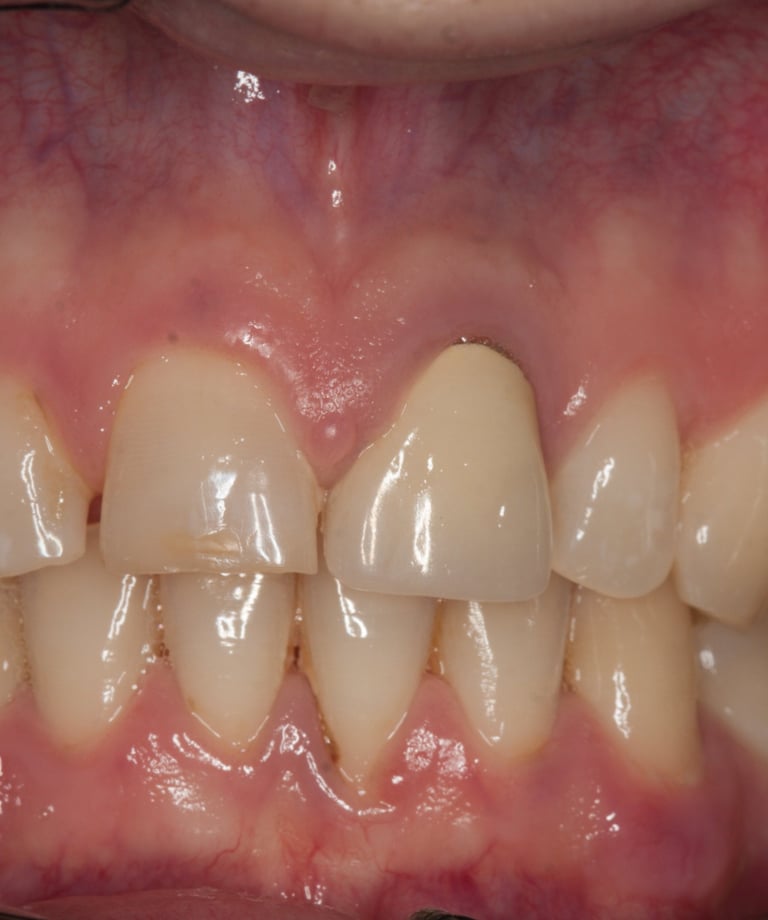

Un paziente si è presentato alla nostra attenzione con un problema di decementazione ripetuta della corona su un incisivo centrale superiore (dente 21). Oltre all'evidente instabilità protesica, la corona mostrava una discrepanza estetica marcata rispetto ai denti naturali adiacenti, compromettendo l'armonia del sorriso.

Dopo un'approfondita analisi clinica e radiografica, sono stati individuati i seguenti problemi:

Corona incongrua: non solo non si armonizzava con i denti circostanti, ma risultava anche inadeguata dal punto di vista funzionale.

Trattamento endodontico inadeguato: il precedente trattamento canalare era insufficiente, lasciando il dente vulnerabile a infezioni e compromettendone la prognosi a lungo termine.

Perno moncone inadeguato: la mancanza di stabilità del perno esistente causava la continua decementazione della corona, rendendo necessario un intervento risolutivo.

Corona Incongrua

Condizioni Iniziali

Moncone non ritentivo